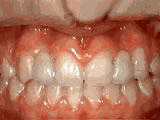

Crowding of the teeth

Patient started treatment at age 11 and wore braces for 26 months. He loves his new smile.